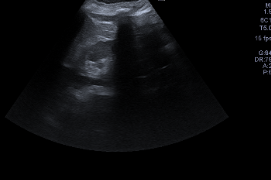

Ecografía abdominal:

Hígado y bazo normales, vesícula alitiásica, riñones normales. Páncreas con porción cefálica engrosada, contornos irregulares y ecogenicidad heterogénea, con áreas hipodensas sugestivas de edema y leve líquido peripancreático. No hay líquido libre intraperitoneal significativo.